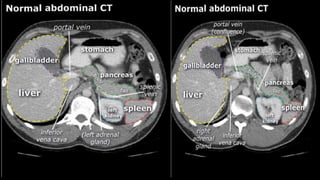

• A few characteristics of normal anatomy:

• Portal venous phase: the parenchyma of the

liver/spleen/pancreas is homogeneously enhanced.

• Intra-abdominal fat has the density of fat (HU -50 to -100;

see the X-ray/CT technique course for more information

about Hounsfield units); similar to normal subcutaneous fat.

If not, there may be ascites or fatty infiltration.

• A fewcharacteristics of normal anatomy: • Portal venous phase: the parenchyma of the liver/spleen/pancreas is homogeneously enhanced. • Intra-abdominal fat has the density of fat (HU -50 to -100; see the X-ray/CT technique course for more information about Hounsfield units); similar to normal subcutaneous fat. If not, there may be ascites or fatty infiltration.